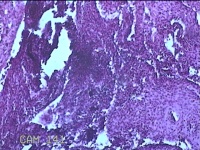

宫颈管组织

性别

女

年龄

33岁

临床诊断

异位妊娠

一般病史

停经52天,阴道流血12天。

标本名称

大体所见

灰白暗红色不规则碎组织4.3x3.3x1.2cm一堆。

图2